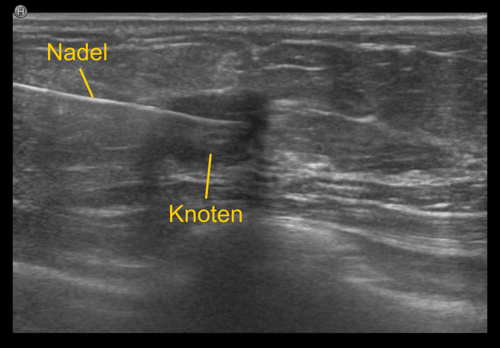

Bei der Gewebeprobeentnahme, der sogenannten 'Biopsie', wird eine dünne Nadel in den verdächtigen Bezirk eingebracht, und eine oder mehrere Gewebeproben entnommen. Diese Proben werden anschließend vom Pathologen aufbereitet und unter dem Mikroskop genau analysiert. Die Entnahmeregion wird üblicherweise mit einem kleinen Markierungsklipp gekennzeichnet, damit die Stelle bei Bedarf jederzeit wieder auffindbar ist.

Die unterschiedlichen Methoden richten sich nach der Bildgebung. Ist die verdächtige Region im Ultraschall sichtbar, wird die ultraschallgezielte Gewebeprobeentnahme bevorzugt, da sie relativ einfach und rasch (üblicherweise zwischen 15 bis 20 Minuten) durchführbar ist.